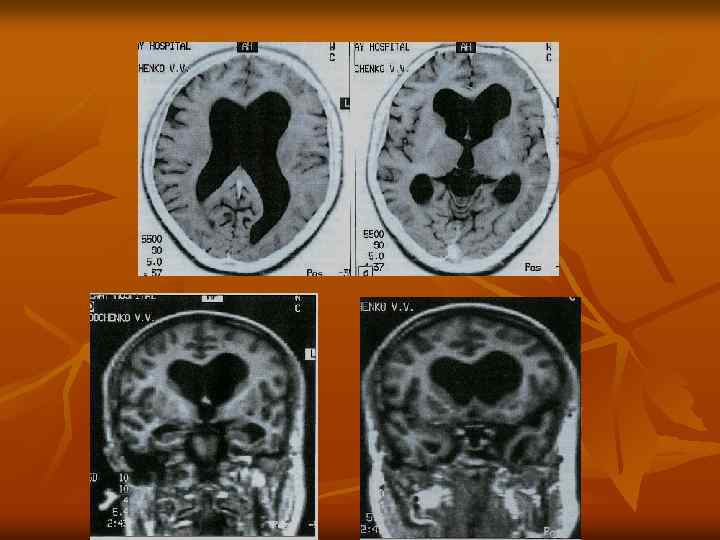

Б-ная В. 43 г. Инв. 2 гр. Д/з Менингиома н/грудного отдела и п/крестцового отделов позвоночника с признаками ликворостаза. Частичная атрофия зрительных нервов обоих глаз, синдром «пустого» турецкого седла, синдром гипоталамогипофизарной недостаточности, психоорганический синдром. Гидроцефалия тривентрикулярная тяжелой степени

Двухфокусная менингиома на уровне ТХІІ и SII, ликворостаз